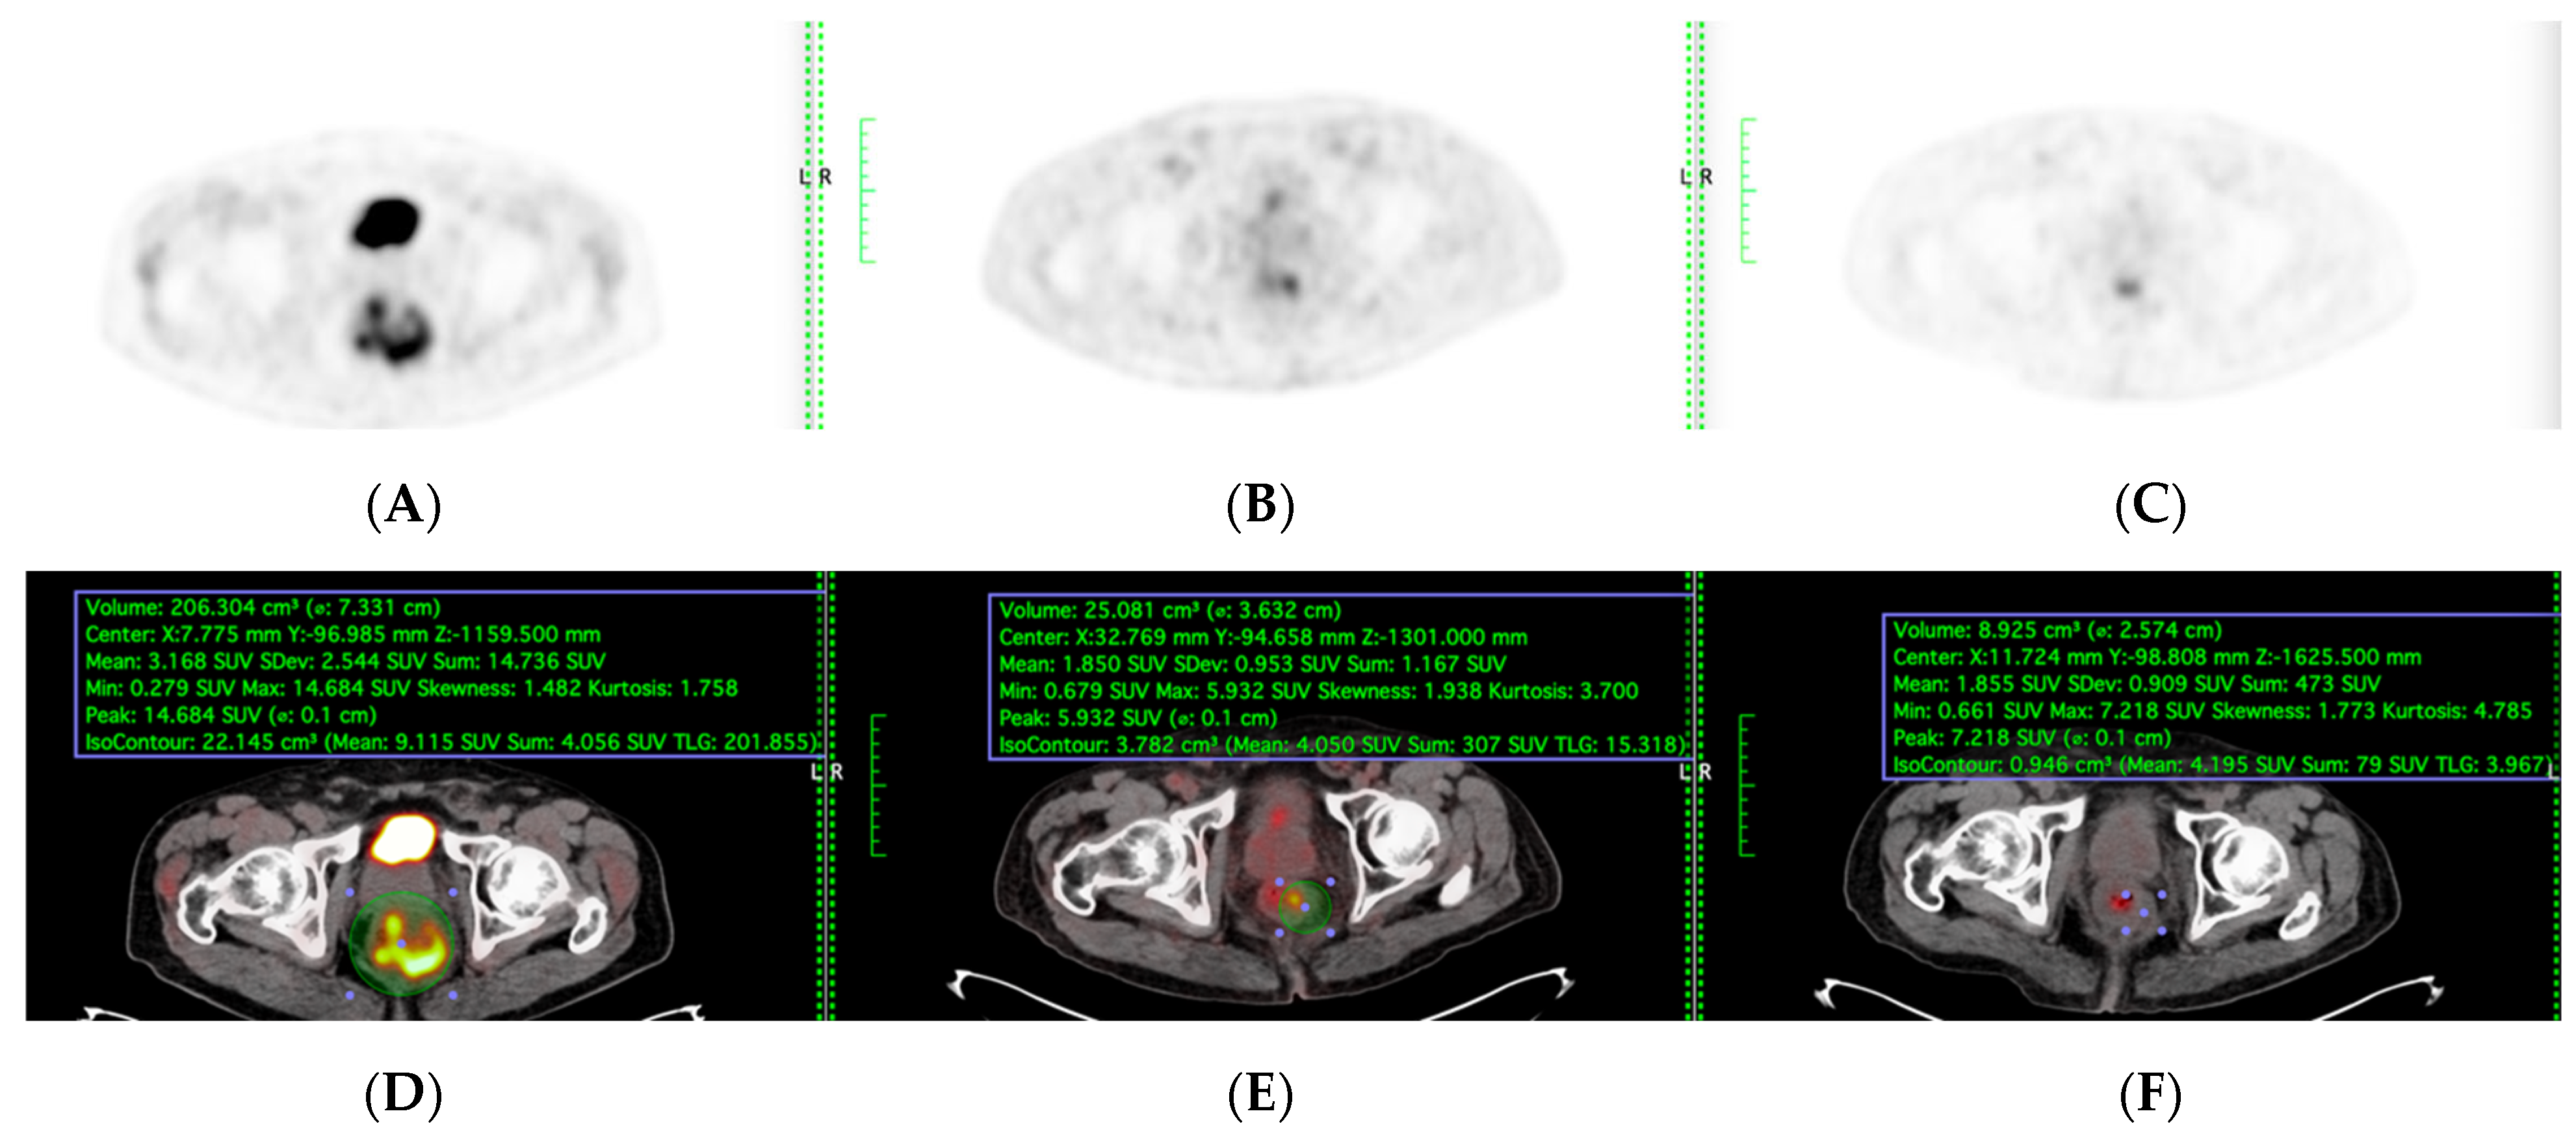

PET-CT, including maximum standardised uptake value (SUVmax) and total lesion glycolysis (TLG), were evaluated among the patients who underwent sequential PET-CT before, during, and after TNT were included (Figure 2). Total Lesion Glycolysis (TLG) was automatically calculated using vendor-specific software by multiplying the metabolic tumour volume (MTV) by the mean standardised uptake value (SUVmean) within the volume of interest (VOI). Lesion boundaries were delineated using a fixed SUV threshold of 2.5 with manual adjustment to exclude physiologic bowel uptake and adjacent organs, consistent with PERCIST guidelines. Sensitivity, specificity, accuracy, and areas under the model’s receiver operating characteristic curve (AUC) were evaluated to determine its performance.

All patients fasted for at least 6 h before the PET/CT scan. Prescanning blood glucose was systematically checked and adjusted to less than 150 mg/dL. Patients received an intravenous injection of 18F-FDG, at a dose of 3.7 MBq/kg of body weight. After 60 min of uptake, the patient was positioned on a flat tabletop, using a movable laser-alignment system, in a “head-first supine” position. A PET-CT scanning of the whole body (six or seven bed positions from head to thigh) was performed using an acquisition time of 2 min per bed position. For each of the PET images, a tumour contour was generated using automated SUVs, which reached threshold levels (SUV > 2.5). The metabolic parameters were acquired and calculated as follows: SUVmax and total lesion glycolysis (TLG). The response is the percentage difference between the results of the baseline PET-CT scan and the results of the other two PET-CT scans) for SUVmax and TLG. SUVmax and TLG were measured at the primary tumour spot (Figure 3).

Figure 2. (A,D) Before, (B,E) during, and (C,F) after TNT PET and PET-CT fusion images were included in TLG quantification. Scanner: Siemens Biograph LSO HI-REZ True-X HD PET-CT.